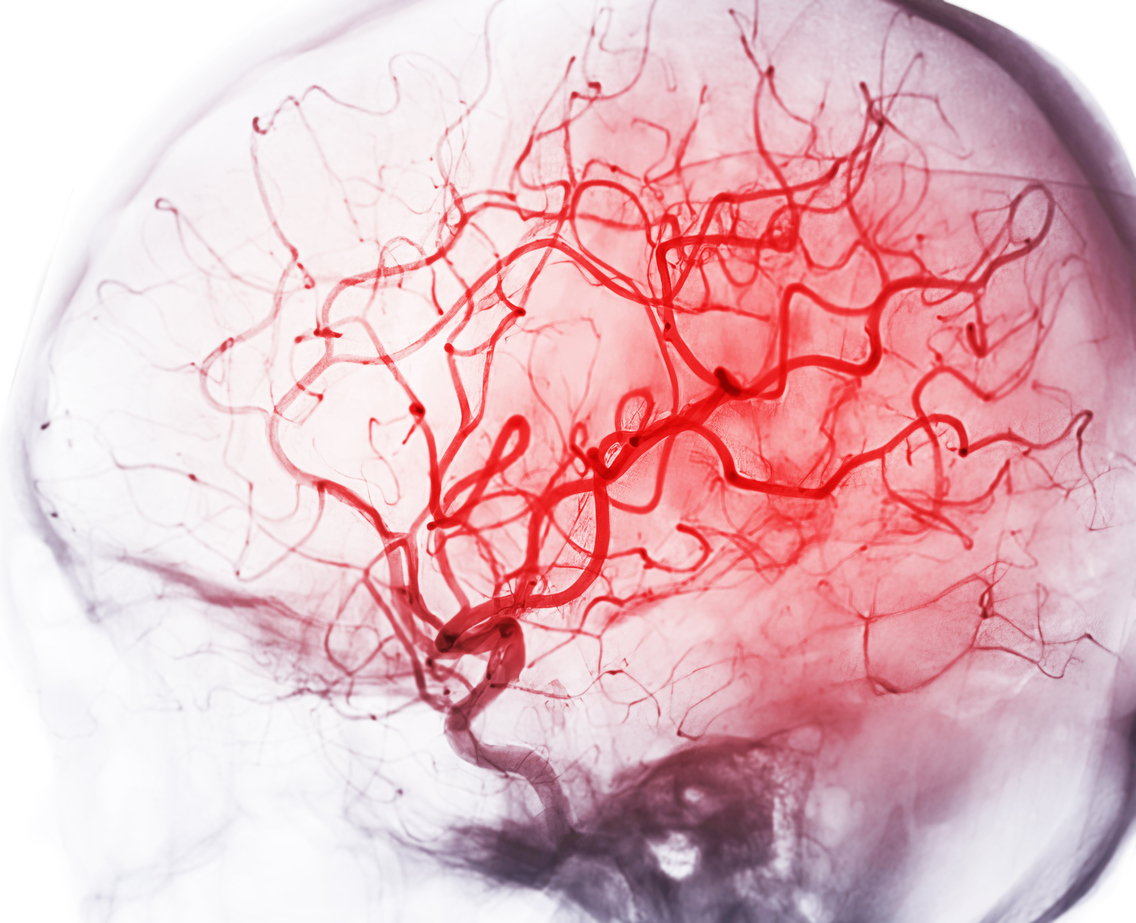

Cerebral angiography image from Fluoroscopy in intervention radiology showing cerebral artery.

Το εγκεφαλικό επεισόδιο μπορεί να αυξήσει σημαντικά τον κίνδυνο εμφάνισης άνοιας και ο κίνδυνος αυτός είναι υψηλότερος κατά το πρώτο έτος έπειτα από ένα εγκεφαλικό, ενώ παραμένει αυξημένος για μια περίοδο 20 ετών.

Εντοπίστηκε ότι ο κίνδυνος άνοιας ήταν σχεδόν τρεις φορές υψηλότερος κατά το πρώτο έτος έπειτα από ένα εγκεφαλικό επεισόδιο, στη συνέχεια μειώθηκε σε μιάμιση φορά αυξημένο κίνδυνο μέχρι την πενταετία και παρέμεινε αυξημένος 20 χρόνια αργότερα.

Άνοια εμφανίστηκε σχεδόν στο 19% των επιζώντων από εγκεφαλικό επεισόδιο κατά τη διάρκεια μιας μέσης παρακολούθησης πεντέμισι ετών.

Επιπλέον, ο κίνδυνος άνοιας ήταν 80% υψηλότερους στους επιζώντες από εγκεφαλικό επεισόδιο σε σχέση με τον γενικό πληθυσμό, αλλά και σε σχέση με την ομάδα ελέγχου που είχε υποστεί καρδιακή προσβολή.

Τέλος, ο κίνδυνος άνοιας σε άτομα που είχαν υποστεί ενδοεγκεφαλική αιμορραγία ήταν σχεδόν 150% υψηλότερος από ό,τι στον γενικό πληθυσμό.